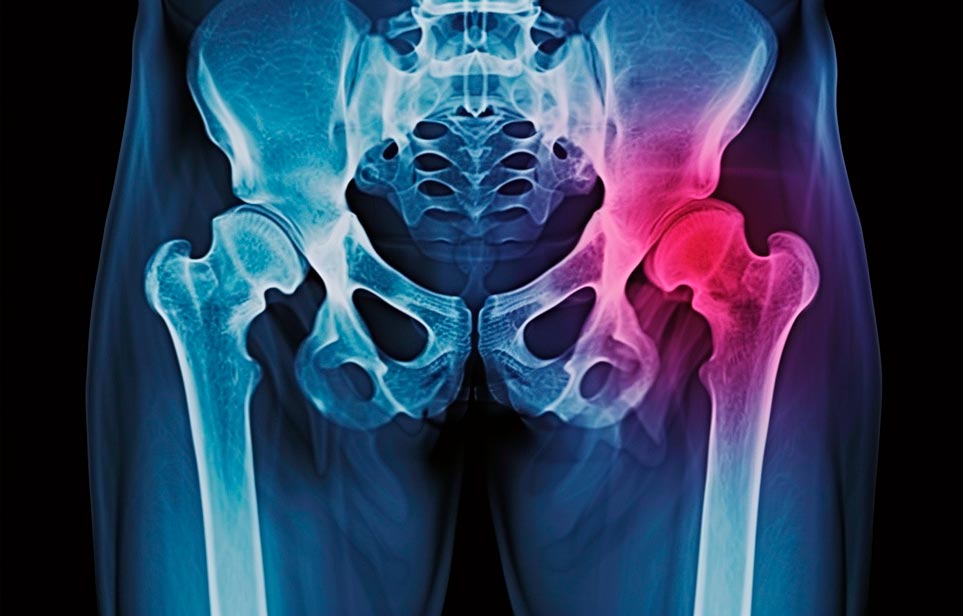

Реабилитация пожилых после перелома шейки бедра в Воронеже

Такая травма в большей части случаев возникает у граждан преклонного возраста. При её появлении на протяжении длительного времени сохраняются болевые и неприятные ощущения в области паха, при которых серьёзно ухудшается качество жизни, возникает множество последствий для его жизни и здоровья.

По какой симптоматике можно определить перелом шейки бедра?

Выявить его можно по возникновению следующей тревожной симптоматики:

- Визуально повреждённая нога сокращается на несколько сантиметром из-за сокращения мышц.

- Стопа выворачивается наружу.

- В лежачем положении человек не может поднять ногу.

При такой симптоматике важно незамедлительно обращаться к специалистам для получения всей необходимой помощи, терапии и восстановления после перелома шейки бедра. Если не оказать помощи старику, то это приведёт к гноению, инвалидности, иным видам осложнений.